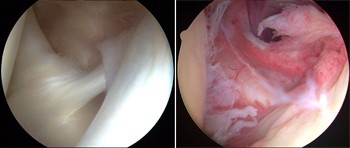

(Left) During arthroscopy, your surgeon inserts the arthroscope and small instruments into your shoulder joint.

(Right) An arthroscopic view of the inside of the shoulder joint.

(Left) An arthroscopic view of a healthy shoulder joint. (Right) In this image of a rotator cuff tear, a large gap can be seen between the edge of

the rotator cuff tendon and the humeral head.

The tendon has been re-attached to the humeral head with sutures.